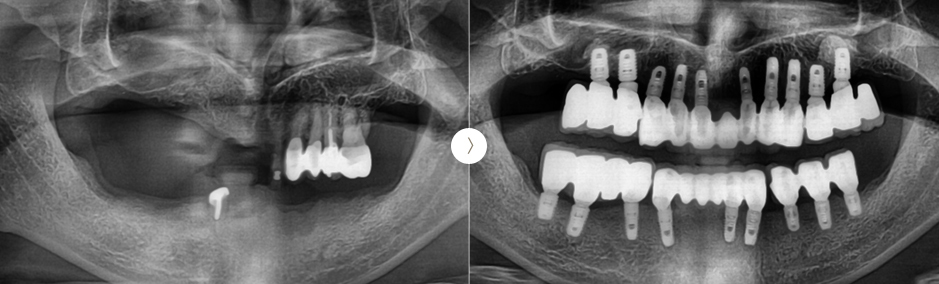

👤 전악 임플란트 CASE

자연치아가 충치나 잇몸질환, 사고 ,노화 등 다양한 이유로 전부 소실되었을 때 치아가 상실된 부위에 임플란트를 식립하여 원래 자연 치아처럼 고정식으로 치아를 모두 재현해 주는 것을 말합니다. 전악 임플란트의 경우 임플란트 틀니에 비해 식립된 임플란트의 개수가 월등히 많기 때문에 저작력이나 고정력이 더 높습니다. 하지만 전악 임플란트는 치조골이 충분해야 가능하고, 임플란트의 개수가 많은 만큼 능숙한 실력을 요하는 고난도 임플란트입니다.